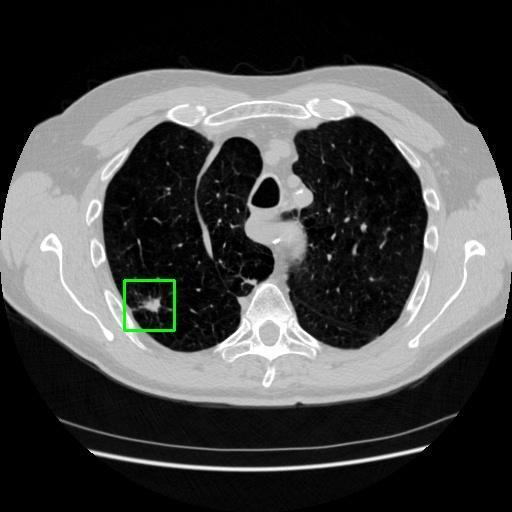

We developed an AI-based system using deep learning models for analyzing lung CT scans to detect and classify pulmonary nodules. We chose the YOLOv11 architecture for its enhanced object detection capability and adapted it specifically for medical imaging, incorporating pixel-level precision and severity classification.

Classification into three severity levels with colored bounding boxes.

Designed a severity classification system that categorizes nodules into null, moderate, and severe using colored bounding boxes, assisting in rapid clinical decision-making.